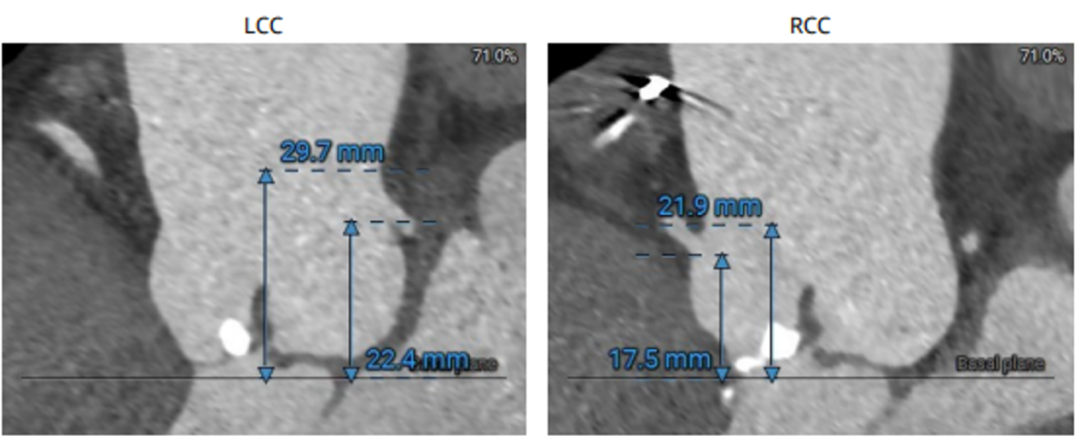

CT结果: